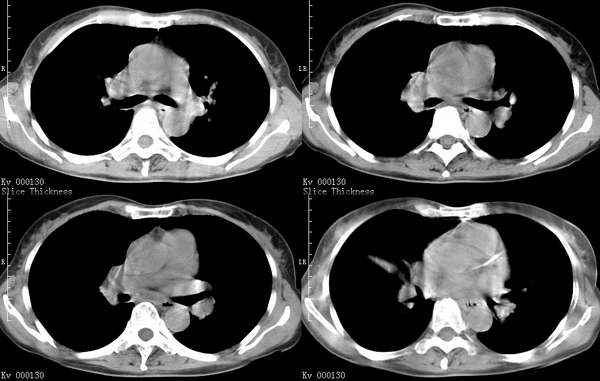

咳嗽6月低热1月!

右上叶背段及左下叶见斑片状密度不均模糊影,右中叶支气管狭窄,中叶密度增高,体积缩小.纵隔未见明确淋巴结.结论:1、两俩结核,右中叶支气管内膜结核,并中叶肺不张。2、两肺炎;右中心型肺癌,并阻塞性肺不张。

右肺上叶尖后段及左肺舌叶 下叶见斑片状密度不均模糊影,右中叶支气管狭窄,中叶密度增高,体积缩小.纵隔未见明确淋巴结。考虑:双肺结核伴右侧中叶不张。

右上叶背段及左下叶见斑片状密度不均模糊影,右中叶支气管狭窄,近端未见肿块,中叶密度增高,体积缩小.纵隔未见明确淋巴结.结论:两肺结核,右中叶支气管内膜结核,并中叶肺不张。肺纹理粗乱,有慢支表现,伴有感染存在。

右中叶支气管内膜结核

考虑结核,右肺中叶考虑支气管内膜结核并中叶肺不张。建议抗结核治疗后复查。

1.右下叶背段结核。2.支气管炎伴双下肺感染。3.右中叶内侧段肺不张。至于原因,考虑支气管内膜结核,建议纤支镜检查。

右上叶及左下叶多发结节状、斑片状阴影。右中叶不张。支持肺结核并右中叶不张。